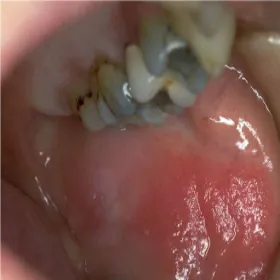

Jama ustna choroby zespół Brandta

Acrodermatitis enteropathica